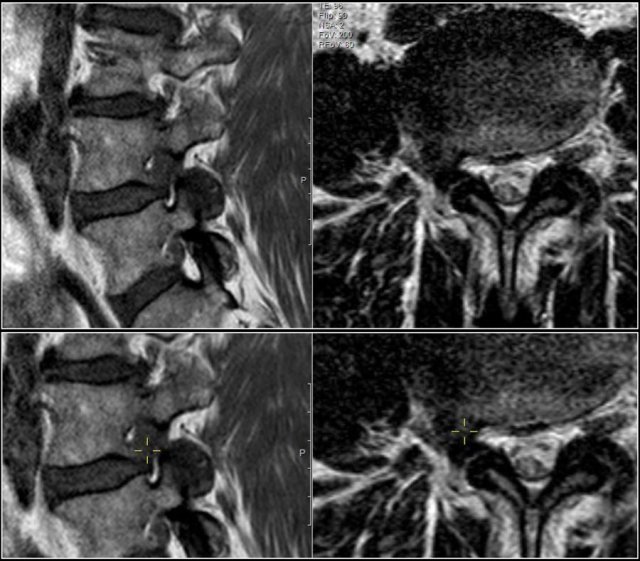

Here a disc herniation with upward migration.

By using the marker, you can correlate the abnormality on the T1W-image with the axial T2W-images.

On the T2W-image it is more obvious that this is a disc herniation.

The lower images are with the marker on.

you may have to enlarge the images to see it.

These foraminal disc herniations can be easily overlooked.

Notice how subtle the findings are on the axial T2W-images.

The herniated disc can be easily mistaken for the nerve root.

The sagittal T1W-image shows the upward migration of the disc.